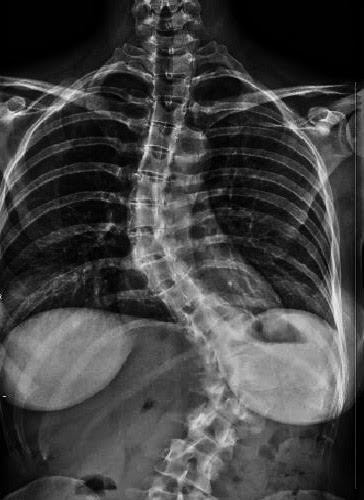

Scoliosis Nightmare Continues…

I know I need to update you guys about my progress and set backs, etc. I promise I will be doing that. However, in the mean time, I wrote this for my other blog, champagnecoloredglasses.com,  and it’s an update on my own little #scoligirl, Emma. Thoughts and prayers are welcome as we take on the […]

F@#! Scoliosis

I feel somewhat guilty that it has taken me this long to write a post. It has been emotional and sometimes difficult to navigate through this mess called scoliosis and what it’s doing to my family. I wanted to wait until I had more information and calmed down before writing an emotionally charged post while […]